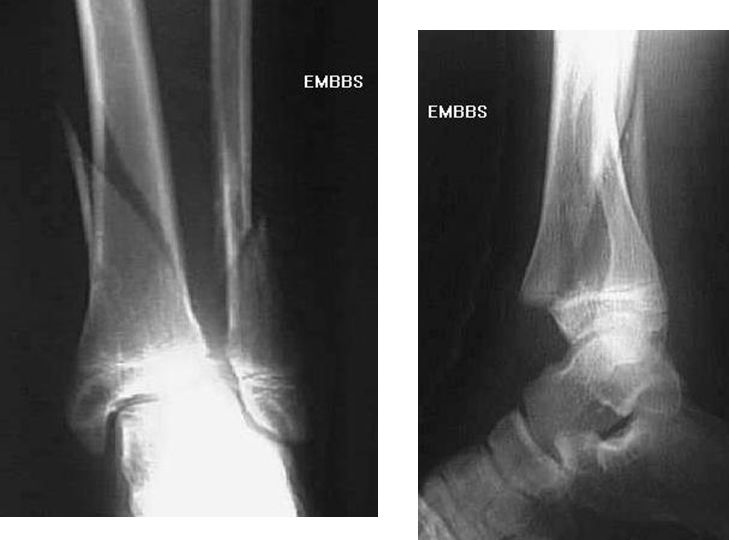

踝关节骨折

三踝骨折

踝关节脱位